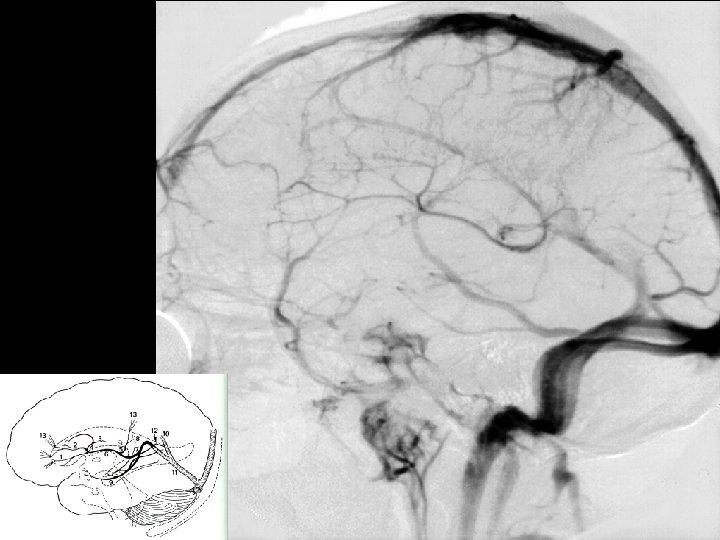

Angiographic digression to aid the understanding of venous angiography Michigan Neurosurgery

Late Venous phase Michigan Neurosurgery

Deep Veins Thalamostriate vein Internal Cerebral vein (2) Vein of Galen Septal vein Basal vein of Rosenthal (2) Occipital vein (2) Posterior Pericallosal vein (2) Mesencephalic vein (2) Precentral Cerebellar vein (1) Inferior Sagittal Sinus Straight Sinus Michigan Neurosurgery